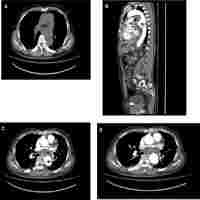

| Abstract | A 51-yr-old man presented exertional dyspnea as a consequence of iliocaval fistula combined with paradoxical pulmonary embolism and high-output heart failure. Endovascular stent-graft repair was performed to cover iliocaval fistula and restore the heart function. After the procedure, dyspnea was improved and procedure related complication was not seen. A 6-month follow-up computed tomography showed regression of pulmonary thromboembolism and well-positioned stent-graft without graft migration, aortacaval communication or endoleak. Stent graft implantation should be considered an alternative of open repair surgery for treament of abdominal arteriovenous fisula, especially in patient with high risk for surgery. |